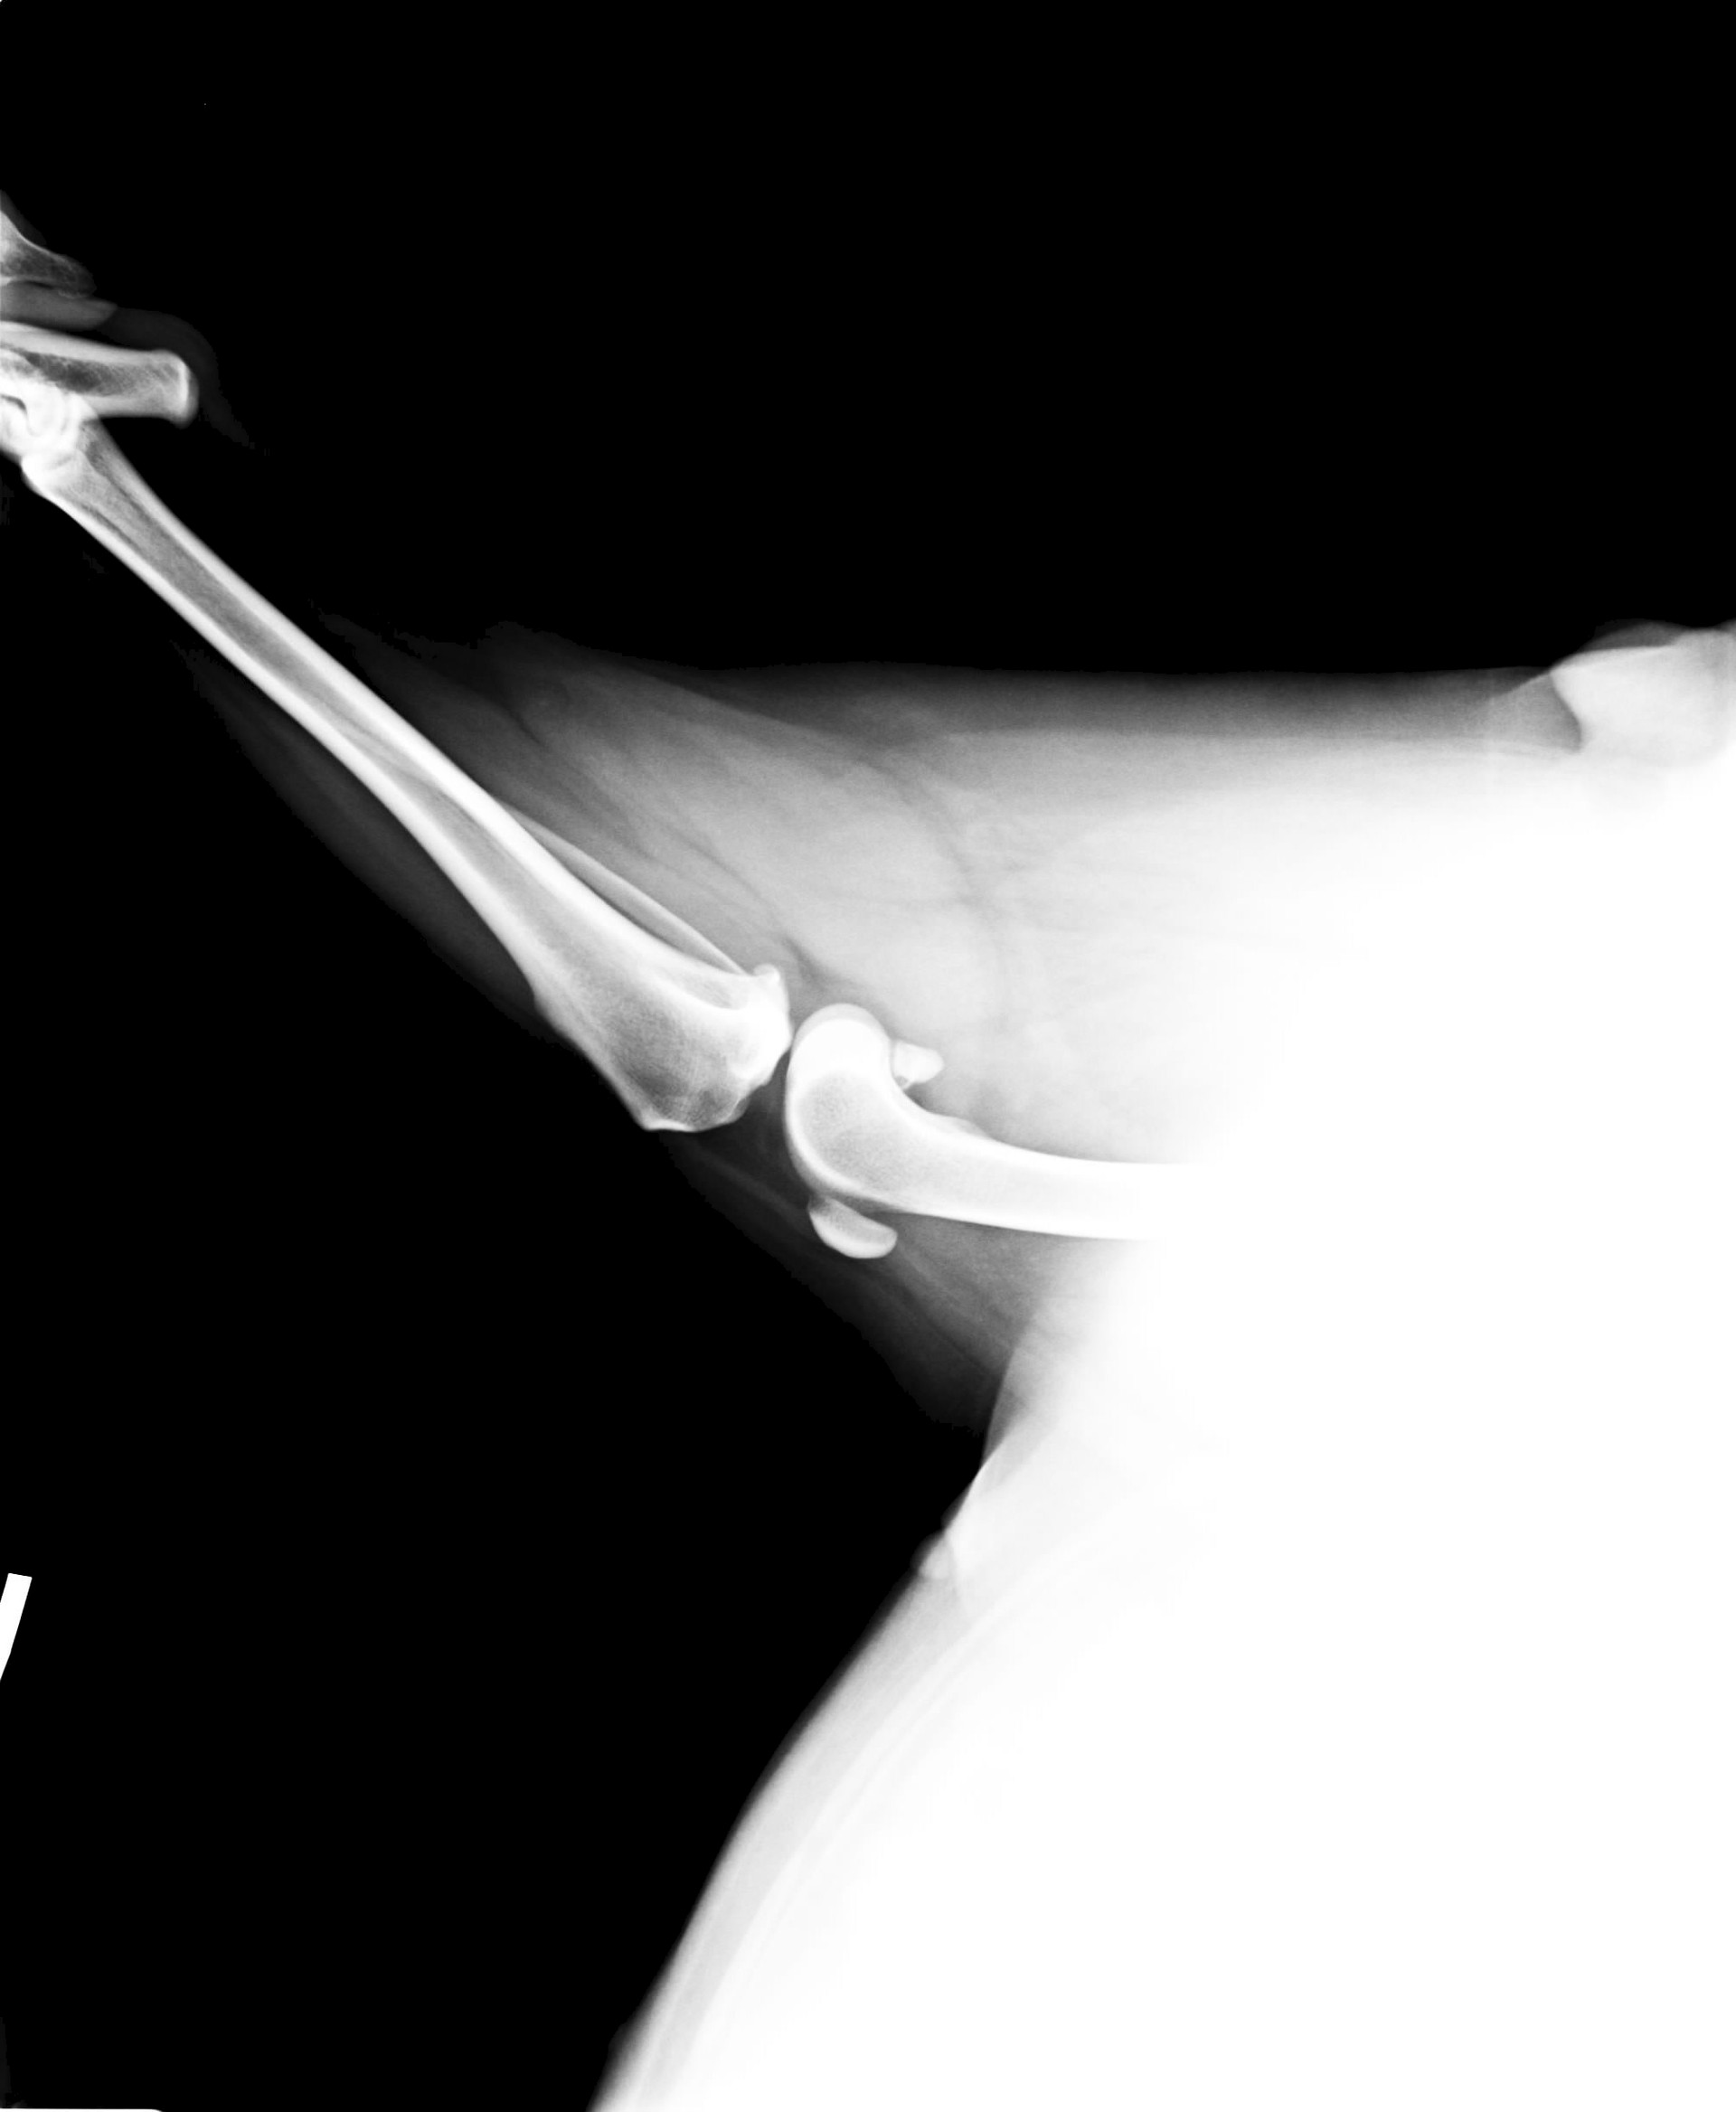

Только что на прогулке собака на ровном месте взвизгнула и стала подгибать левую заднюю лапу. Думала стекло ледышка или что -нить другое, нет подушечки чистые. Далее стало понятно, что это колено (потрескивает сильно).

Кое как доковыляли домой, собака крупная, в апреле 7 лет. Раза два обращались в Зооцентр, по причине - иногда, незначительная хромота в задней лапе (кстати лапа та же

). Итог: наверно отлежала, само пройдет...